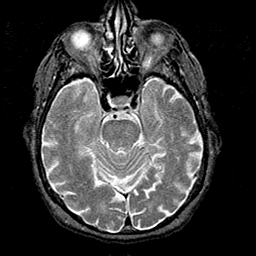

Alzheimer's disease MR T2-weighted -- Slice #16

[Home][Help][Clinical][Tour 1][Tour 2] Slice 16